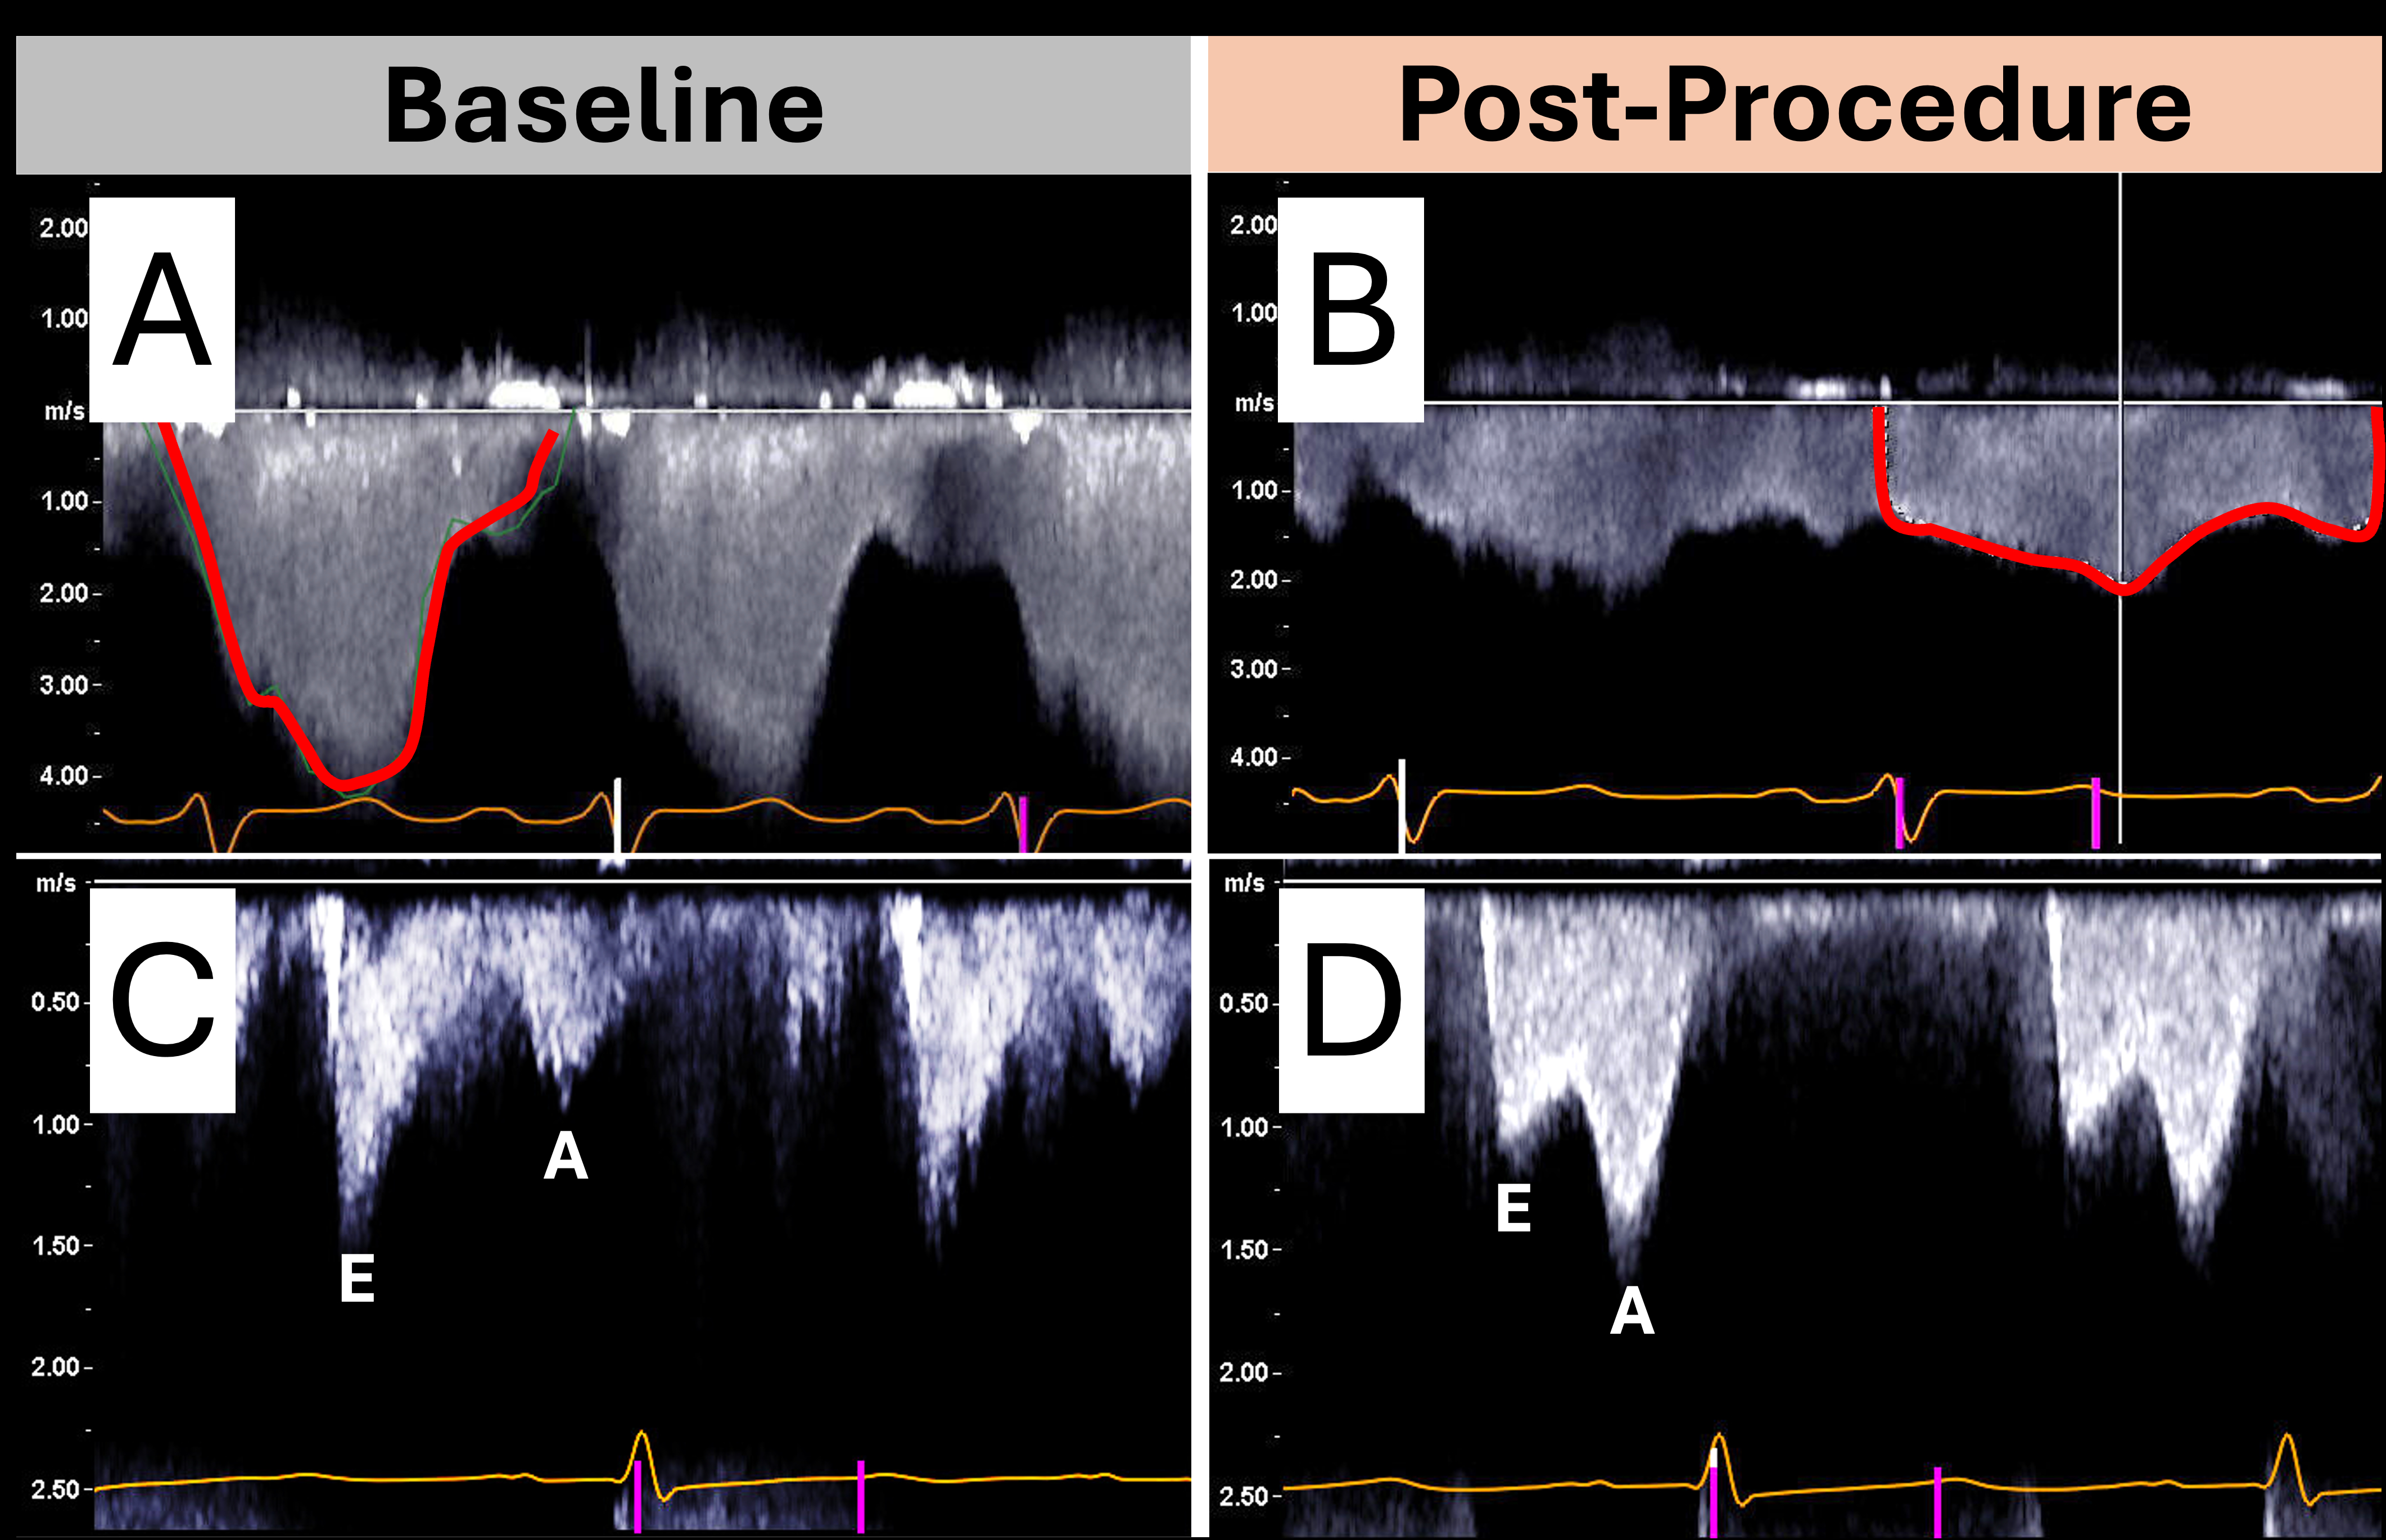

Case 2: A 53-year-old man with severe functional MR had a dense, early-peaking with low-Vmax, triangular MR jet on spectral Doppler and a peak/mean iatrogenic atrial septal defect (ASD) gradient of 72/28 mm Hg. Post-TEER, the MR jet became parabolic with low Vmax and less dense, and the ASD gradient dropped to 16/9 mm Hg.

Key echocardiographic indicators of resolved severe MR post-intervention include: (1) marked reduction in jet area on color Doppler, (2) increased LVOT stroke volume indicating improved forward flow, (3) transition from a dense, low-Vmax, triangular MR jet contour to a less dense, high Vmax, parabolic MR jet contour on spectral Doppler reflecting improved LA hemodynamics, (4) decreased transseptal pressure gradient across the iatrogenic ASD reflecting improved LA pressure, (5) shift from E-wave to A-wave dominant mitral inflow in the absence of significant mitral stenosis, (6) return of antegrade pulmonary S wave flow reflecting decreased LA pressure, and (7) reappearance of LAA SEC, as the MR jet no longer washes away the SEC seen in chronic atrial fibrillation. While no single measure is definitive, these findings support a multimodal approach to residual MR assessment and highlight the need for further validation.